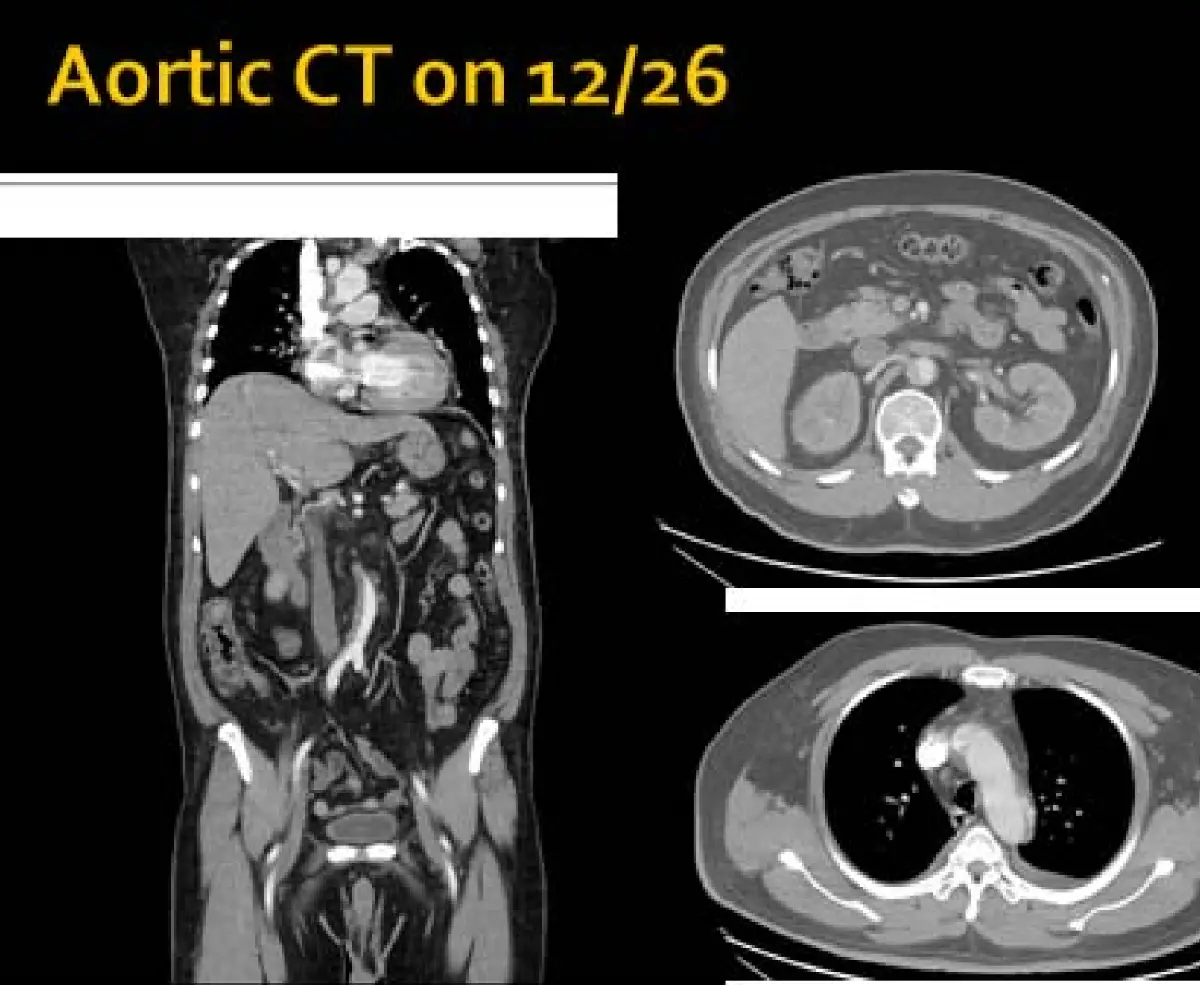

本題考核主動脈剝離(aortic dissection)的綜合診斷,整合急性胸痛病史、極高血壓、心電圖(無 STEMI 型態)、胸部X光(縱膈增寬)、主動脈 CT(確認剝離與內膜片)及實驗室數據(腎功能受損),訓練考生在多線索情境下做出正確鑑別診斷。

影像分析: